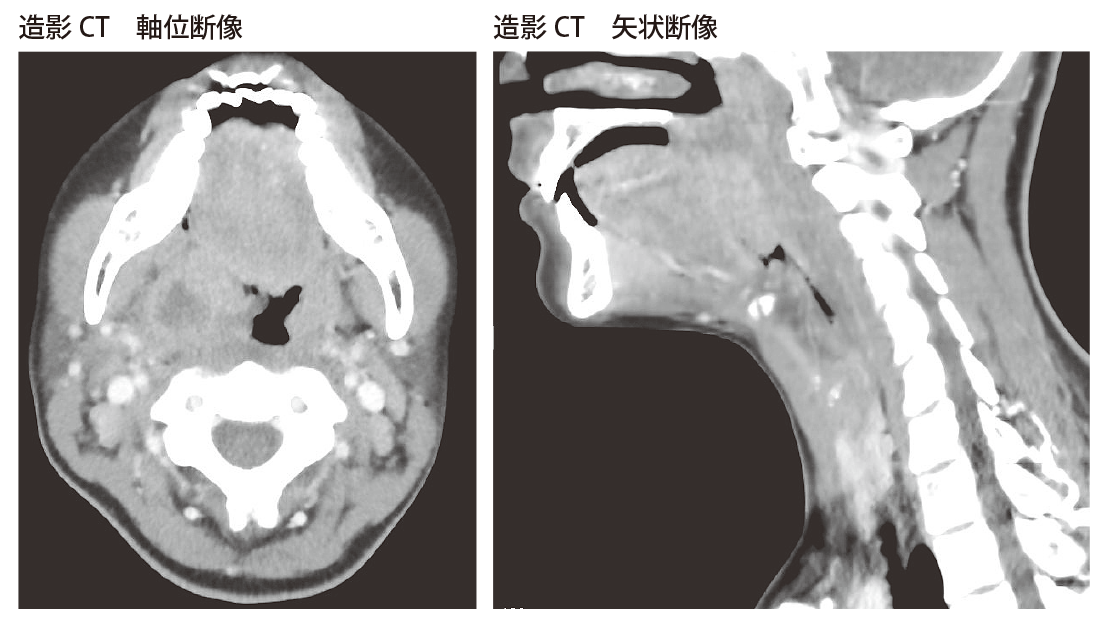

Chapter 2 頭頸部がんの検査と診断 頭頸部がん がん免疫 Jp Immuno

父の癌細胞が消滅したct Mri画像 難病 末期癌からの生還